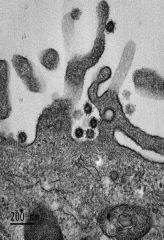

Vignette (© Philippe Roingeard et Sébastien Eymieux, Université de Tours).